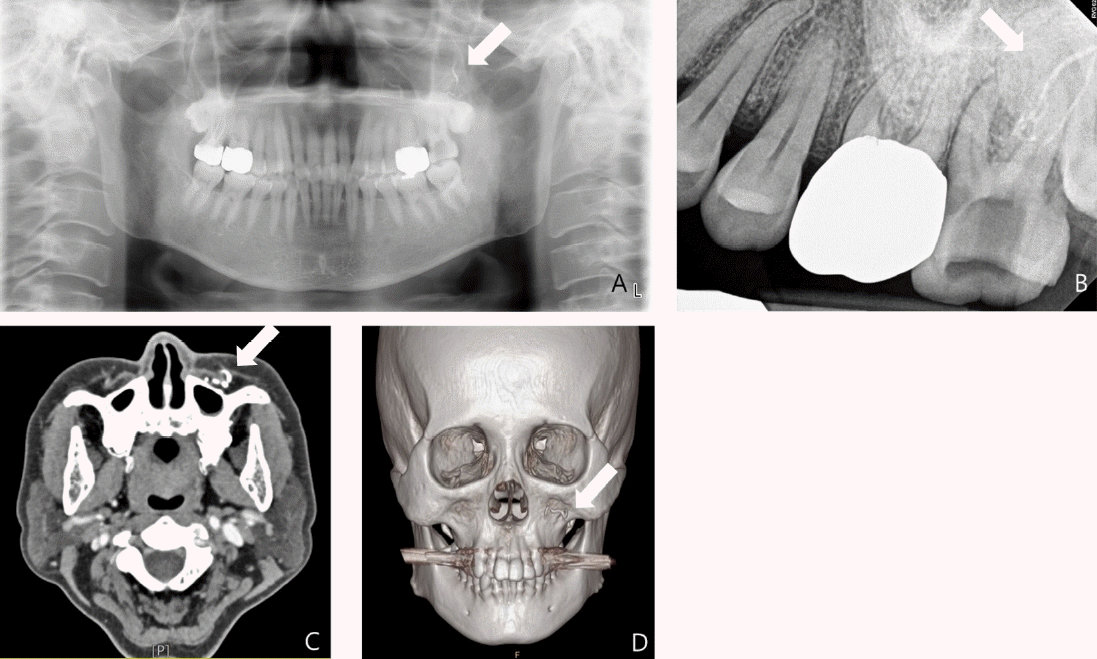

Fig. 2.

Radiographic examination performed at the initial examination. A and B. Periapical and panoramic views show extrusion of calcium hydroxide paste beyond the root apex of the left maxillary second molar (arrows). C and D. Facial angio computed tomography demonstrate loss of contrast in the posterior superior alveolar artery, indicating arterial obstruction (arrows).